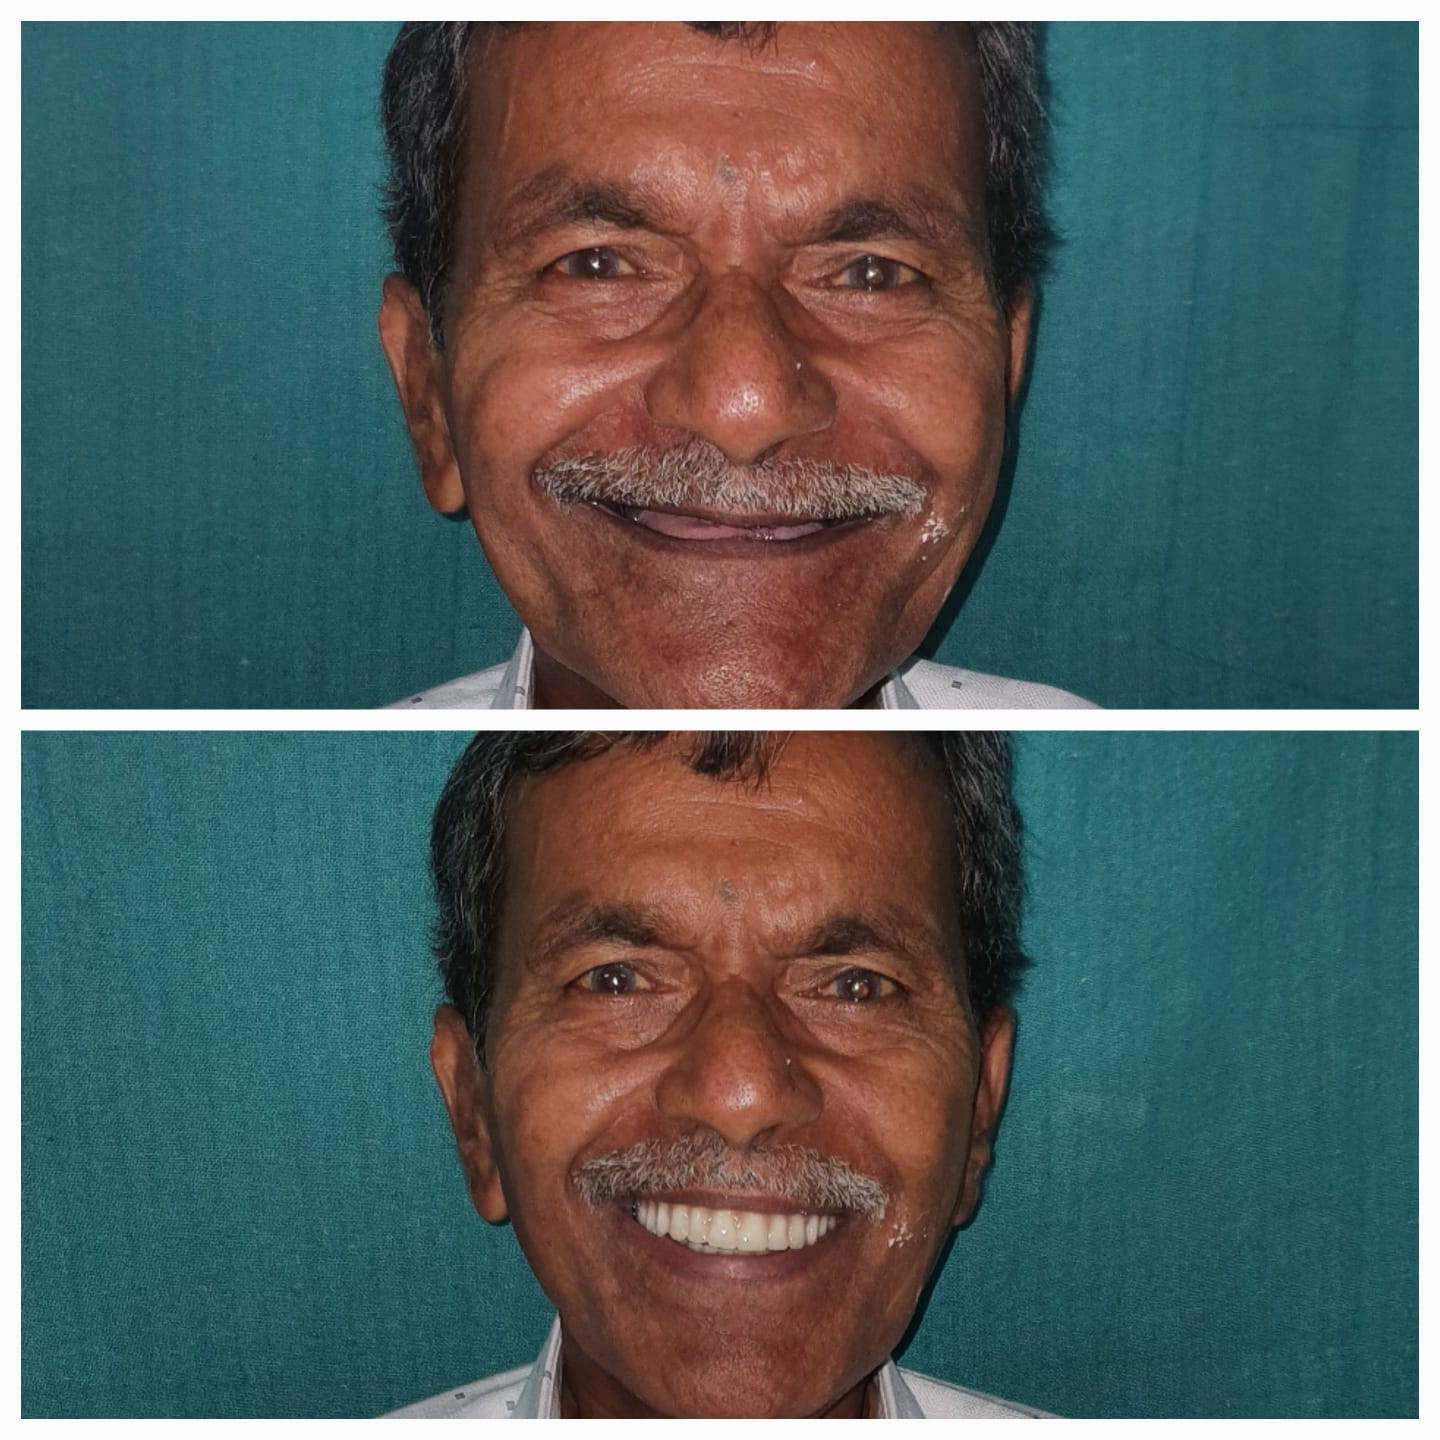

Smile Transformation Results

Real patient results showcasing confident, healthy, natural smiles.

Explore Our Care Moments

Discover insightful visuals highlighting smile transformations, advanced dental procedures, and patient care at our Hyderabad clinic.